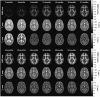

The human brain rapidly develops during the final weeks of gestation and in the first two years following birth. Diffusion tensor imaging (DTI) is a unique in vivo imaging technique that allows three-dimensional visualization of the white matter anatomy in the brain. It has been considered to be a valuable tool for studying brain development in early life. In this review, we first introduce the DTI technique. We then review DTI findings on white matter development at the fetal stage and in infancy as well as DTI applications for understanding neurocognitive development and brain abnormalities in preterm infants. Finally, we discuss limitations of DTI and potential valuable imaging techniques for studying white matter myelination.